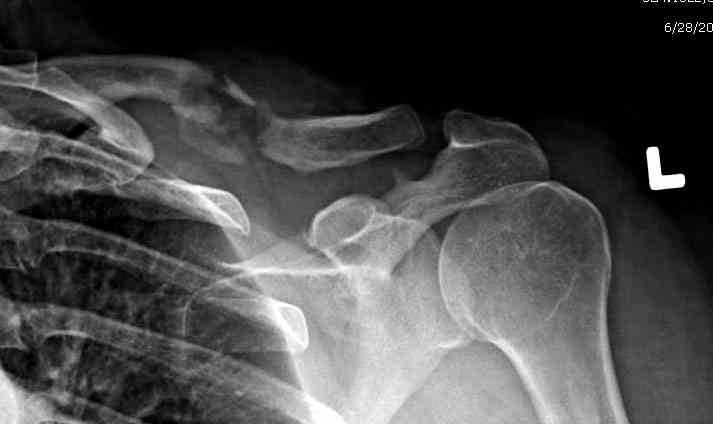

iГГШ> выполнения новокаиновой блокады дежурной бригадой выполнена закрытая

ГГШ> репозиция, наложены кольца Дельбе. Результаты репозиции показаны на

ГГШ> Результат стационарного лечения приведен на рентгенограмме (Xray_3).

Это картинка то есть через неделю после травмы, при выписке? Более чем приемлемо.

2) стояние фрагментов при выписке идентично таковому при пступлении - с выраженным смещением

Уважаемая Г.В. Полностью согласен с Вашим постом.Закрытая репозиция и кольца Дельбе отлично зарекомендовали себя за 35 лет практики. В обсуждаемом случае представленные Р-граммы сами говорят за себя, 1 снимок (до лечения) и 3 снимок (после лечения) абсолютно идентичны, 2 снимок сделан в несколько иной позиции.Как говорится "комментарии излишни". Согласитесь, что результат лечения мог бы быть и лучшим.